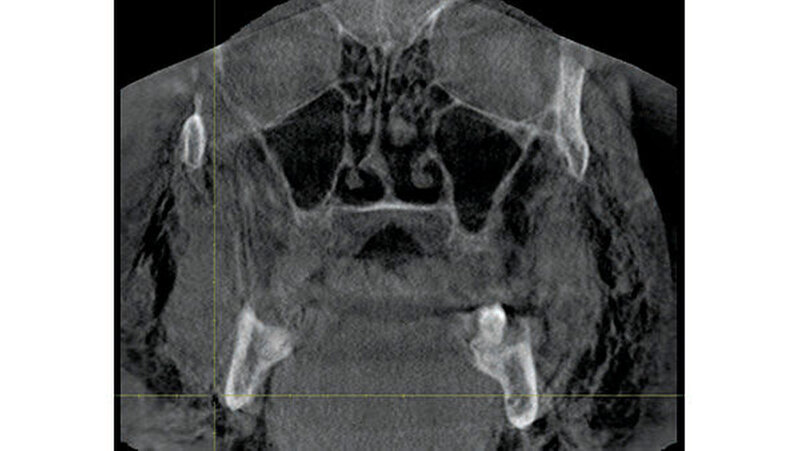

Zum Ausschluss einer Mittelgesichtsfraktur bei palpatorischem Weichteilemphysem erfolgte zur weiteren Diagnostik eine DVT-Aufnahme. Es zeigten sich keine Frakturen im Bereich des Mittelgesichts oder der Kiefer. Jedoch kam in der DVT-Bildgebung sowie der OPT-Optik ein massives Weichgewebeemphysem zur Darstellung (Abbildungen 2 bis 5).